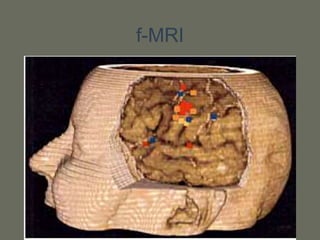

f-MRI